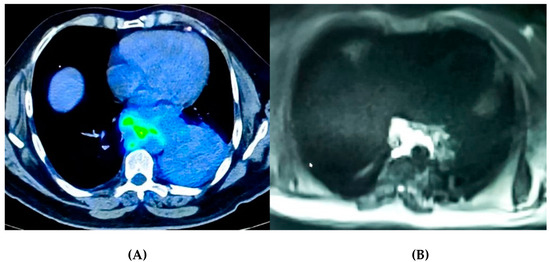

2.2. Imaging as a Tool to Assess Tumor Micro-Environment

- Martini, K.; Frauenfelder, T. Old Borders and New Horizons in Multimodality Imaging of Malignant Pleural Mesothelioma. Thorac. Cardiovasc. Surg. 2021. [Google Scholar] [CrossRef]

- Armato, S.G.; Blyth, K.G.; Keating, J.J.; Katz, S.; Tsim, S.; Coolen, J.; Gudmundsson, E.; Opitz, I.; Nowak, A.K. Imaging in pleural mesothelioma: A review of the 13th International Conference of the International Mesothelioma Interest Group. Lung Cancer 2016, 101, 48–58. [Google Scholar] [CrossRef]

- Ciliberto, M.; Kishida, Y.; Seki, S.; Yoshikawa, T.; Ohno, Y. Update of MR Imaging for Evaluation of Lung Cancer. Radiol. Clin. N. Am. 2018, 56, 437–469. [Google Scholar] [CrossRef] [PubMed]

- Zheng, J.; Gong, X.Q.; Tao, Y.Y.; Wang, R.; Yang, G.; Li, J.D.; Ren, T.; Li, Z.M.; Yang, C.; Wang, W.C.; et al. Correlative Study Between IVIM-DWI Parameters and the Expression Levels of Ang-2 and TKT in Hepatocellular Carcinoma. Front. Oncol. 2021. [Google Scholar] [CrossRef]

- Meyer, H.J.; Wienke, A.; Surov, A. Association Between VEGF Expression and Diffusion Weighted Imaging in Several Tumors-A Systematic Review and Meta-Analysis. Diagnostics 2019, 9, 126. [Google Scholar] [CrossRef] [PubMed]